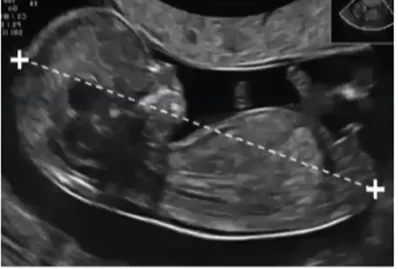

Hội chứng truyền máu song thai (Twin-Twin Transfusion Syndrome - TTTS)